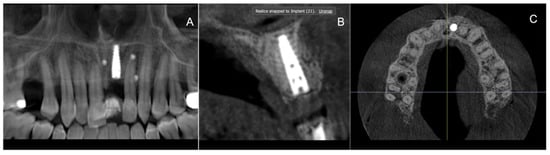

2. Materials and Methods

2.3. Surgical Treatment